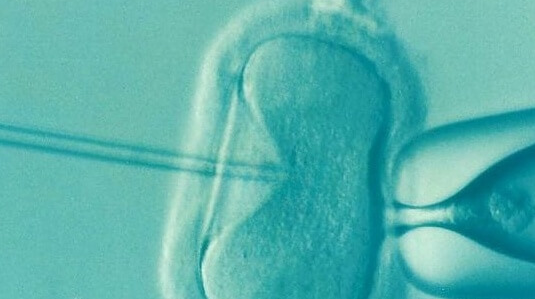

雌激素作为女性体内重要的性激素,对卵泡的发育和成熟起着至关重要的作用。然而,当雌激素水平过高时,卵泡的正常发育过程可能会受到抑制。高雌激素环境可能导致卵泡壁变薄,增加卵泡提前破裂的风险。卵泡破裂不仅意味着卵子提前释放,还可能因未在最佳时机受精而降低受孕概率。此外,雌激素过高还可能干扰卵泡的成熟过程,导致卵泡发育不良,卵子质量下降,从而影响后续的胚胎发育和着床。

卵泡发育不良是雌激素过高的另一严重后果。在正常情况下,卵泡需要经历一系列复杂的发育过程才能成熟并排出卵子。然而,高雌激素环境可能打破这一平衡,导致卵泡发育停滞或异常。卵泡发育不良不仅表现为卵泡大小不达标,还可能伴随卵子形态异常、染色体异常等问题,进一步降低试管婴儿的成功率。